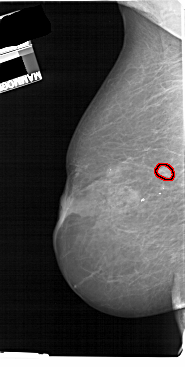

A_1114_1.LEFT_MLO

LEFT_MLO LINES 5491 PIXELS_PER_LINE 2761 BITS_PER_PIXEL 12 RESOLUTION 43.5 OVERLAY

FILE: A_1114_1.LEFT_MLO.OVERLAY

TOTAL_ABNORMALITIES 1

ABNORMALITY 1

LESION_TYPE MASS SHAPE OVAL MARGINS SPICULATED

ASSESSMENT 4

SUBTLETY 3

PATHOLOGY MALIGNANT

TOTAL_OUTLINES 1

BOUNDARY